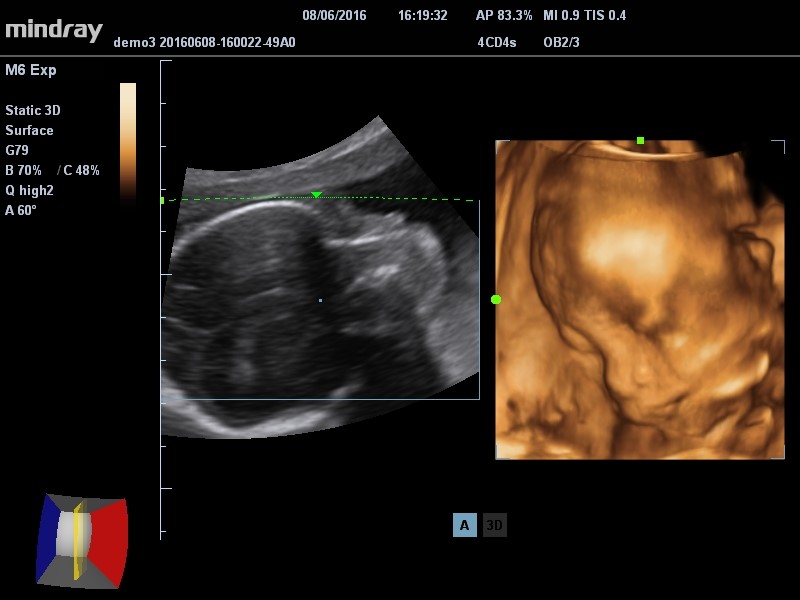

"PREMIUM, EXTENSIVE, ADVANCED" Mindray M6 je dopplerovský ultra lehký přenosný UZV přístroj najvyšší třídy s použitím HD sond. Stress echo. 4D. TDI. Panoramatické zobrazení...

"PREMIUM, EXTENSIVE, ADVANCED"

Mindray M6 je dopplerovský ultra lehký přenosný UZV přístroj najvyšší třídy s použitím HD sond. Stress echo. 4D. TDI. Panoramatické zobrazení...

- nové funkce v 4D zobrazování: Surface (zobrazení tváře plodu), Max (zobrazení páteře), X-ray, Min (zobrazení hepatálních vén), Inversion (zobrazení cév)